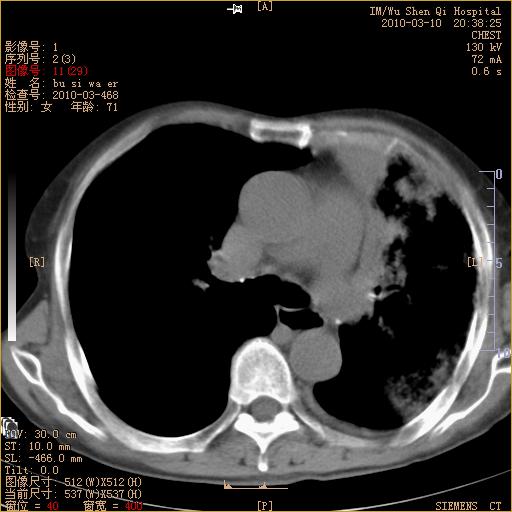

以下是引用随光逐影在2010-3-11 0:41:00的发言:[br]1)考虑左肺及右肺上叶继发性肺结核并左肺炎症感染。2)左侧支气管内膜结核可能;建议必要时行纤支镜检查。3)肺气肿。4)心包膜增厚(或少量心包积液)。5)左侧胸腔积液。